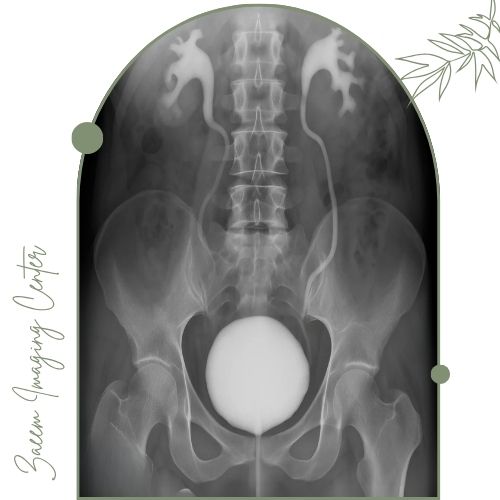

عکس رنگی مثانه (VCUG) چیست؟